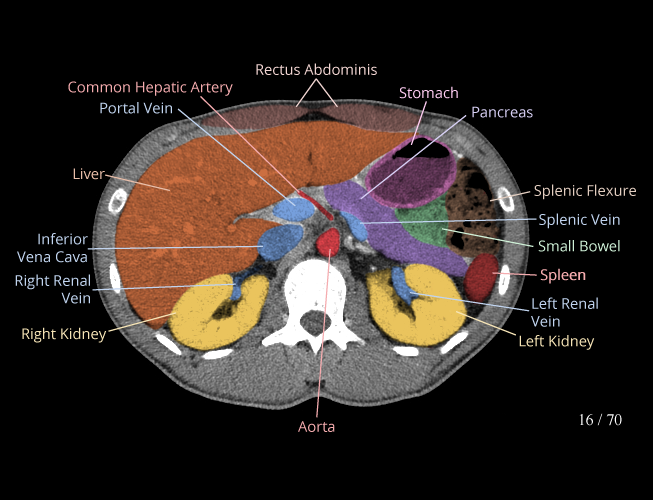

Body

Covers abdominal CT anatomy.